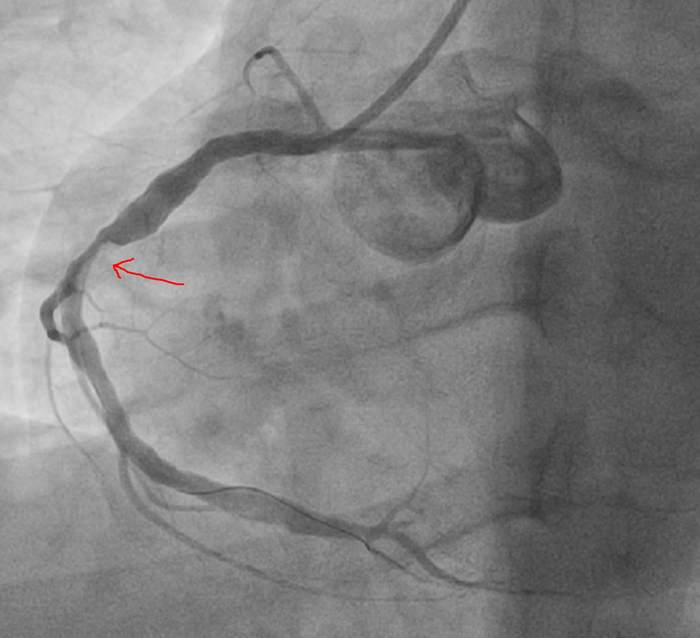

Ко второму курсу училища( училища, а не универа) я уже читал ЭКГ. Все основные случаи инфарктов, аритмий и блокад. Изучал все пленки ЭКГ.